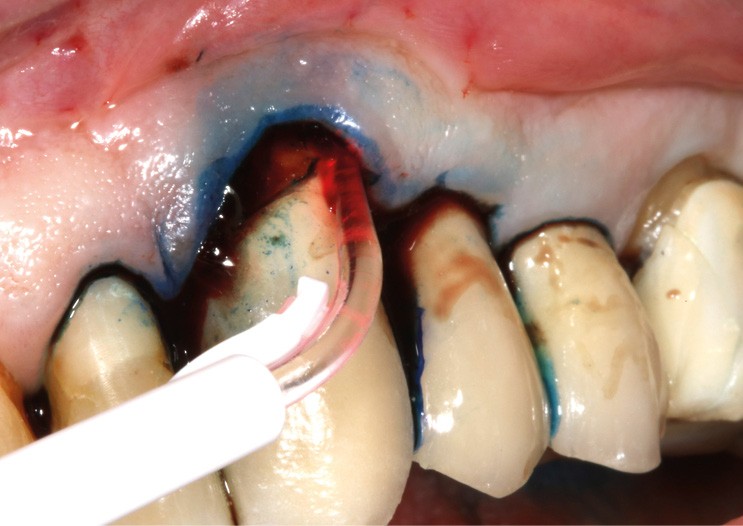

– thérapie photodynamique (bactéricide avec colorant photosensible) pour les lasers de faible énergie (600 à 800 nm),

- Parmi ces longueurs d’onde, deux lasers (Er-YAG et Diode) sont intéressants dans le traitement de la péri-implantite :

– Le laser Er-YAG, utilisé pour le nettoyage, est un laser avec un milieu actif composé d’yttrium, d’aluminium et de grenat dopé à l’erbium. Avec une longueur d’onde de 2 940 nm situé dans l’infrarouge, le laser Er-YAG est un laser à haute énergie, dont la lumière est absorbée dans l’eau et dans l’hydroxyapatite et qui ne pénètre pas profondément. Ceci permet de couper des tissus mous et des tissus durs, mais également de désorganiser le biofilm bactérie.

C’est un laser idéal pour le traitement chirurgical des péri-implantites. Il permet l’élimination du tissu de granulation à la surface de l’implant et de l’os ainsi qu’une décontamination mécanique par effet photoablatif.– Le laser Diode, utilisé pour la décontamination…